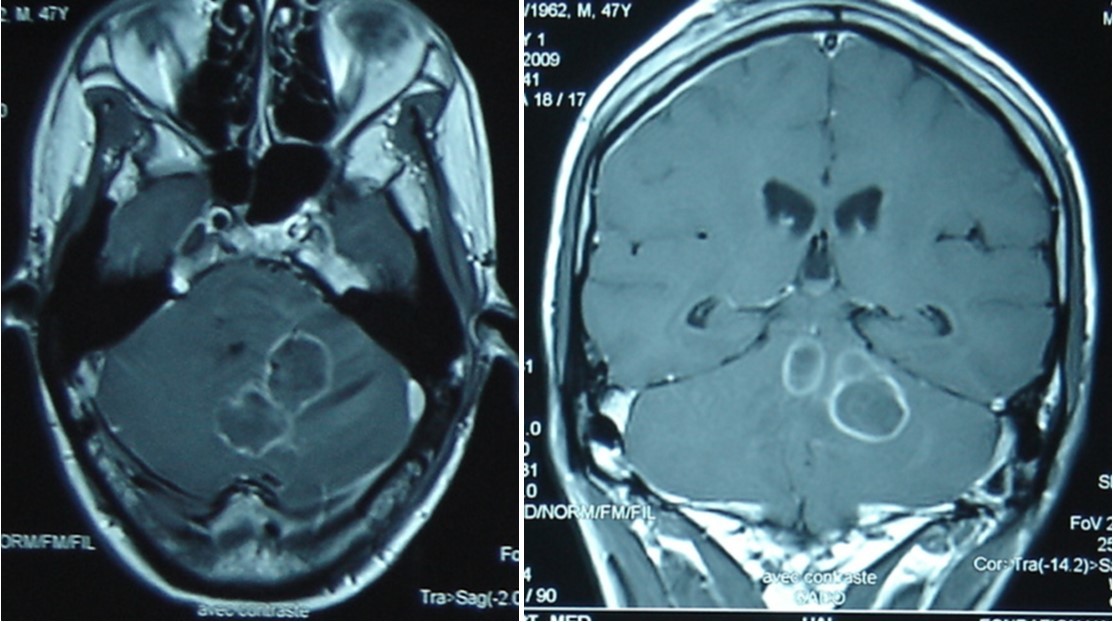

A 47 year old patient with no previous medical history presented with features of raised intracranial pressure, statokinetic cerebellar syndrome as well as left sided hemiparesis. The diagnosis of posterior fossa space occupying lesion was made. Neuroradiologic investigations demonstrated posterior fossa lesions. Magnetic resonance imaging and spectroscopy were in favor of a multiple infective process (Figure 1). Stereotatic biopsy was carried out on the patient and parasitological and histological examinations of the specimen concluded to a filamentous fungal infection of Aspergillus type. Culture and staining techniques categorized the specie as Aspergillus fumigatus (Figure 2).

Figure 1.cerebral MRI axial T1-weighted (A) and coronale (B), showing a multiples well circumscribed posterior fossa lesions